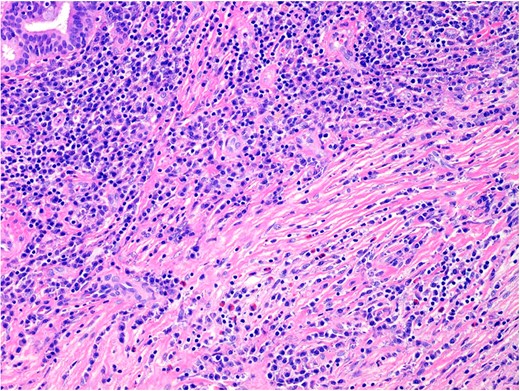

Histopathology demonstrated stromal storiform and perivascular concentric fibrosis with a prominent chronic inflammatory infiltrate (Fig. 2). This consisted of mature lymphocytes, mature plasma cells and eosinophils (Fig. 3). Arteritis (a feature of GPA) was not seen. On digital microscopy, the IgG4 plasma cell counts were 98–120/HPF and IgG4:IgG ratios of 0.4–0.7.

Sinonasal mucosa showing marked chronic inflammation and stromal fibrosis. 40× magnification. H&E.